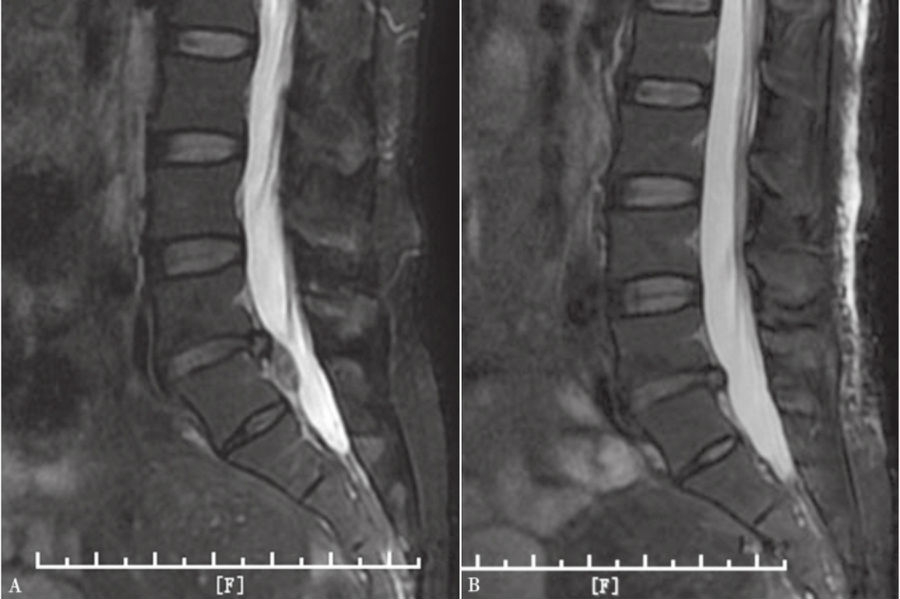

9. 术后复查MRI。(图43、图44)

图44 术前和术后MRI核磁共振矢状位对比

A. 术前腰椎MRI矢状位;B.术后腰椎MRI矢状位